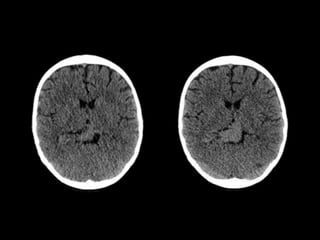

TC CEREBRAL SIMPLE

08-06-2023.

TC SIMPLE DE CRANEO

08/06/2023

Lesión ocupante de espacio extraaxial

supratentorial a nivel de cisterna cuadrigeminal.

CONCLUSIONES:

ESTUDIOS REALIZADOS: TC CEREBRALSIMPLE 08-06-2023. RNM CEREBRAL 20-06-2023.

TC SIMPLE DECRANEO 08/06/2023

Lesión ocupante deespacio extraaxial supratentorial a nivel de cisterna cuadrigeminal. CONCLUSIONES: